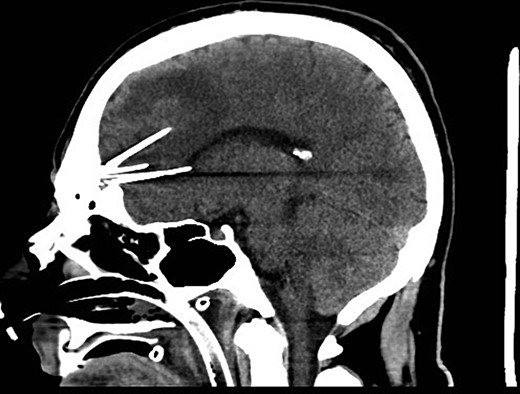

Following the current presentation, he was commenced on levetiracetam and a CT angiogram was performed to rule out an intracranial vascular injury. A preoperative CT slice and three-dimensional (3D) reconstruction of the needles in-situ is provided in Figs 1 and 2.

Preoperative sagittal CT demonstrating six needles traversing through the frontal lobe.